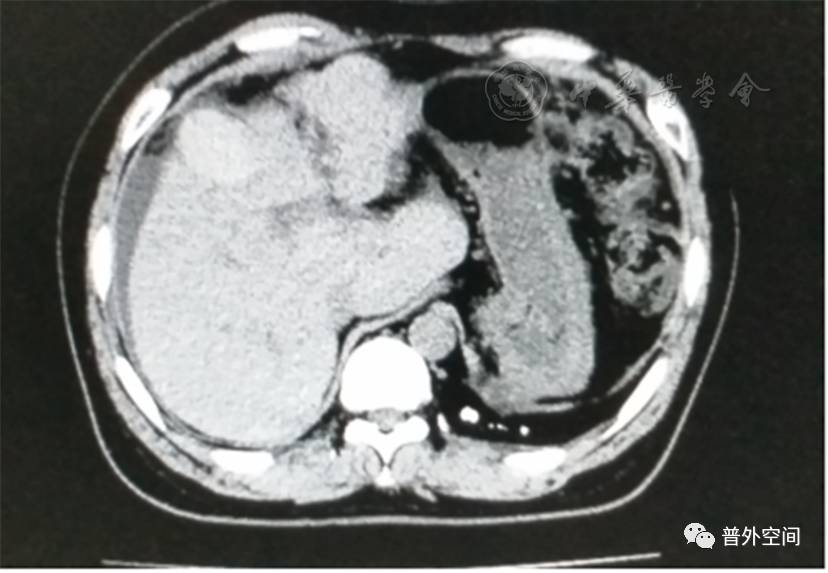

我们将这种方法应用到100多例没有艾滋病病毒感染的一般肝硬化患者身上,结果收到更好的疗效。例如1例男性患者,56岁,失代偿期肝硬化大量腹水合并脐疝(见封四,图1)。CT检查提示肝脏明显萎缩,肝脏体积1 302 ml,大量腹水,脾脏肿大(见封四,图2)。在多家医院就诊后都认为需要做肝移植。我们对患者进行脾切除加脐疝修补,自体骨髓经门静脉输注治疗。手术后3个月,肝功能Child-Pugh分级从C级转成*级A**,手术后1年,肝功能正常,腹部伤口愈合良好(见封四,图3)。CT检查提示肝脏明显增大,体积1 796 ml,腹水基本消失(见封四,图4)。对于肝功能C级的患者手术风险比较高,围手术期输注白蛋白、凝血酶原复合物、纤维蛋白原,改善肝脏功能,手术中经胃网膜右静脉插管埋置骨髓输注装置,输注自体骨髓。随着自体骨髓干细胞在肝内发生复杂的变化,肝硬化组织中的胶原纤维被降解和吸收,肝脏组织的增生和体积增大,肝功能好转,门静脉压力会逐渐降低。但是在手术后1年内,仍然有可能随时发生上消化道出血,需要经胃镜检查,套扎食管黏膜下明显曲张的静脉血管。这样我们做脾脏切除解除脾功能亢进,不做贲门周围血管离断,减少了手术损伤。食管黏膜下静脉曲张用胃镜下套扎治疗。待肝硬化逐渐逆转,食管黏膜下静脉曲张程度将会逐渐减轻。

图4 1年后对比手术前同一部位CT断层照片